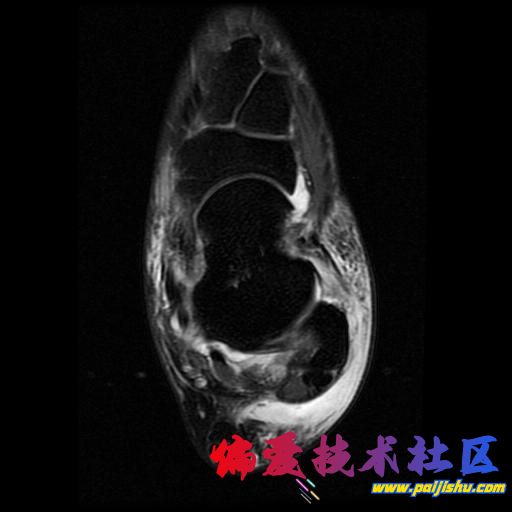

庆幸骨头没事,单肌腱拉伤,静养中